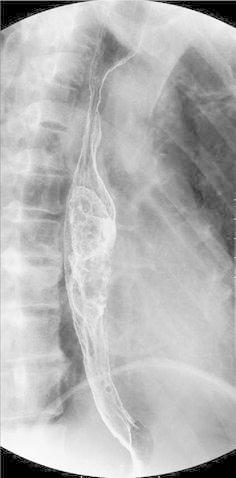

Upper gastrointestinal contrast radiography: a pedunculated polypoid tumor was identified in the mid-thoracic esophagus (Fig. 3).

Fig. 3.

Upper gastrointestinal contrast radiography shows a pedunculated tumor in the mid-esophagus